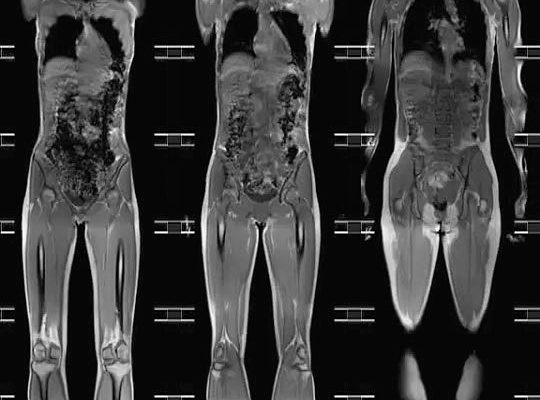

МРТ всего тела позволяет выявить скрытые патологические процессы на ранней стадии развития. Это тест, который оценивает состояние органов и тканей организма, распознает патологию и определяет степень развития болезненного процесса.

Магнитно-резонансная томография дает возможность получить подробную информацию о состоянии пациента без боли, ущерба для здоровья и потери времени.

Магнитная томография всего тела выявляет нарушения целостности органов и тканей, очаги воспаления и гнойные, врожденные и приобретенные патологические явления, скопление жидкости в полостях органов. Этот же метод используется при диагностике заболеваний коронарных артерий, изменений структуры печени, а также при мониторинге состояния аневризм аорты.

Диагностика магнитным резонансом всего тела длится полчаса до часа (в зависимости от конкретного клинического случая). Поиск опухолей обычно длится дольше, в отличие от комплексного исследования МРТ. Это связано с необходимостью получения подробных изображений с наличием тонких сечений внутренних органов.